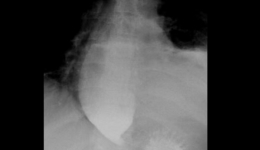

打通生命通道-消化中心为贲门失弛缓患者行内镜微创POME手术37岁中年男性因为吞咽困难加重2年多慕名到消化中心知名专家门诊找江学良教授就诊,2年前由开始吃馒头等固体食物出现吞咽梗阻感,逐渐发展到喝稀饭也出现吞咽困难,伴呕吐咳嗽,夜间加重,...